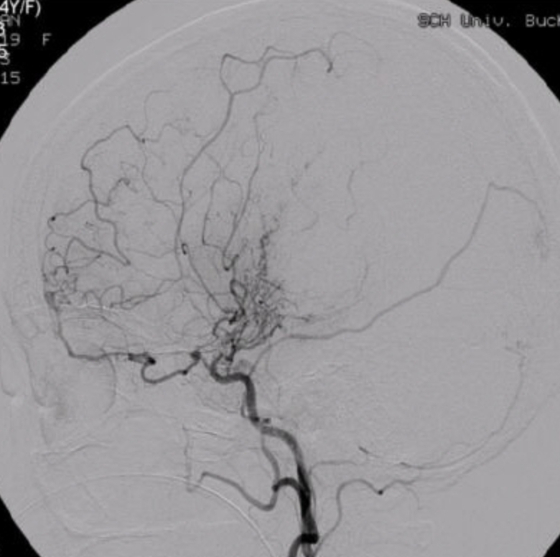

모야모야병은 뇌로 가는 주요 혈관이 좁아지거나 막히면서 발생한다. 병명의 모야모야(もやもや)는 '희미하게 피어오르는 연기'를 뜻하는 일본어로, 이상 혈관 모양이 마치 연기가 피어오르는 것처럼 생겨 붙은 이름이다. 혈관이 막히면 뇌에 산소와 영양 공급이 차단돼 뇌경색이 발생하고 약해진 혈관이 터지면 뇌출혈로 이어질 수 있다.

다만 혈류를 회복시키는 뇌혈관 우회술(재건술)의 수술 효과는 뚜렷한 편이다. 수술 후 환자 85~95%가 뇌 혈류 개선 양상을 보였고 70~90%에서 일과성 허혈증과 허혈성 뇌졸중이 줄어들 수 있다. 출혈형 모야모야병 재발 위험도 절반 넘게 감소한단 보고가 있다. 이 교수는 "국내 모야모야병 환자는 인구 10만명당 약 16명으로 결코 드문 질환이 아니고 진단 환자도 늘고 있다"며 "의심 증상이 있다면 재빨리 병원을 방문해 정밀검사 및 적절한 치료를 받아야 한다"고 강조했다.